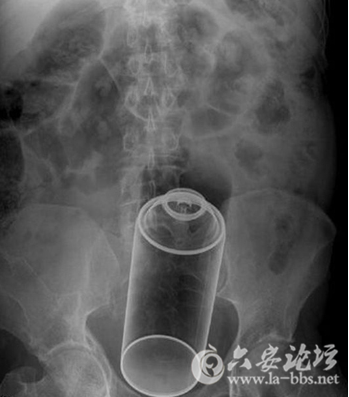

这些让人瞠目结舌的X光片,映射出了女人下体的那点儿事儿,对性有需求是好的,可是要是乱放东西,伤到身体,那可麻烦大了!

这是一瓶专门用来出汗的止汗剂瓶身吗?

16.5CM长的按摩棒状的东西,看形状,是女性理想的自慰用具,不过要掌握力度,适可而止最好!